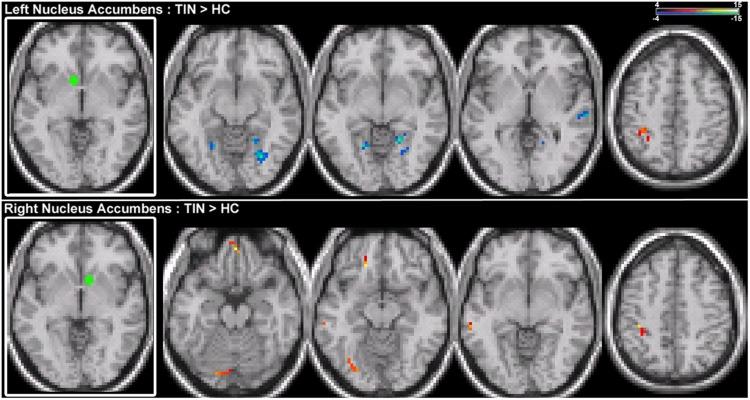

Tinnitus is a common auditory perceptual disorder whose neural substrates are under intense debate. One physiologically based model posits the dorsal striatum to play a key role in gating auditory phantoms to perceptual awareness. Here, we directly test this model along with the roles of auditory and auditory-limbic networks in tinnitus non-invasively by comparing resting-state fMRI functional connectivity patterns in chronic tinnitus patients against matched control subjects without hearing loss. We assess resting-state functional connectivity of the caudate dorsal striatum (area LC), caudate head (CH), nucleus accumbens (NA), and primary auditory cortex (A1) to determine patterns of abnormal connectivity. In chronic tinnitus, increases in ipsilateral striatal-auditory cortical connectivity are found consistently only in area LC. Other patterns of increased connectivity are as follows: (1) right striatal area LC, A1, CH, and NA with parietal cortex, (2) left and right CHs with dorsal pre-frontal cortex, (3) NA and A1 with cerebellum, hippocampus, visual and ventral pre-frontal cortex. Those findings provide further support for a striatal gating model of tinnitus, where dysfunctionally permissive area LC enables auditory phantoms to reach perceptual awareness.

耳鸣是一种常见的听觉感知障碍,其神经基础存在激烈争论。一种基于生理学的模型认为背侧纹状体在将听觉幻像门控至感知意识方面起关键作用。在此,我们通过比较慢性耳鸣患者与无听力损失的匹配对照受试者的静息态功能磁共振成像(fMRI)功能连接模式,直接非侵入性地测试该模型以及听觉和听觉 - 边缘网络在耳鸣中的作用。我们评估尾状核背侧纹状体(LC区)、尾状核头部(CH)、伏隔核(NA)和初级听觉皮层(A1)的静息态功能连接,以确定异常连接模式。在慢性耳鸣中,仅在LC区一致地发现同侧纹状体 - 听觉皮层连接增加。其他连接增加的模式如下:(1)右侧纹状体LC区、A1、CH和NA与顶叶皮层,(2)左右CH与背侧前额叶皮层,(3)NA和A1与小脑、海马体、视觉和腹侧前额叶皮层。这些发现为耳鸣的纹状体门控模型提供了进一步支持,其中功能失调的允许性LC区使听觉幻像能够达到感知意识。